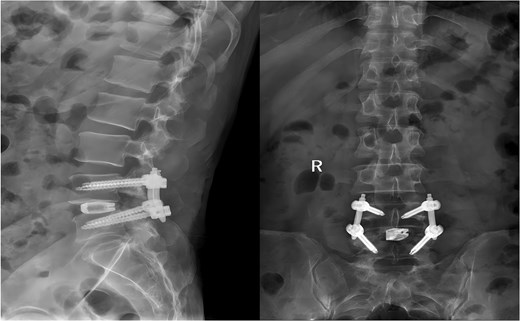

A 49-year-old male presented with a 10-month history of low back pain accompanied by numbness in the left lower limb. Over the past 2 weeks, his symptoms had progressively worsened without any identifiable precipitating factor, with increasing pain and numbness radiating down the left lower extremity. The patient reported that walking about 20 meters aggravated his symptoms, which were relieved after rest, allowing him to walk another short distance before the pain recurred. Due to the lack of significant relief from over-the-counter analgesics and topical medications, he presented to our outpatient clinic for further evaluation. Clinical examination and preoperative imaging demonstrated lumbar spinal stenosis at the L4/L5 level, lumbar instability, and grade I spondylolisthesis at L4 (Fig. 1). Following a comprehensive preoperative assessment, the patient was scheduled for PE-PLIF.

Preoperative anteroposterior and lateral radiographs of the lumbar spine.

Following the surgery, the patient remained in stable condition with no reported discomfort. Postoperative radiographs verified complete extraction of the guidewire, with no residual fragments observed at the fracture site (Fig. 6). The patient experienced an uneventful recovery, and subsequent follow-up evaluations demonstrated satisfactory outcomes.

Postoperative anteroposterior and lateral radiographs of the lumbar spine.